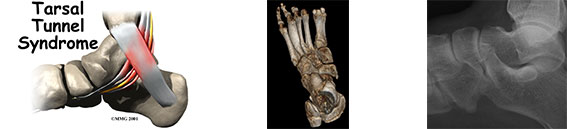

- Neuropatie (Joggera, Baxtera) i nerwiaki.

14.30-16.00 Metody badania stawu skokowego, stopy i ścięgna Achillesa: RTG, USG, artrografia, TK, MR, artro-TK i artro-MR oraz ich zastosowanie w podstawowych patologiach.

9.00-10.00 Uszkodzenia kostne i chrzęstno-kostne stawu skokowego i stopy.

10.00-11.00 Skręcenia i niestabilność stawu skokowego i trochę patologii ścięgien.